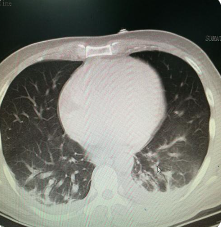

胸腔积液一般是由什么疾病造成的,该如何诊治(图2)

(二)结核性胸膜炎

结核性胸膜炎是由结核分枝杆菌引起的疾病。结核病是一种慢性传染病,可侵犯多个器官,包括肺部。当结核分枝杆菌侵入胸膜并引起炎症时,胸腔内会产生积液。结核性胸膜炎的特点是积液呈现为混浊的外观,同时伴随着结核病的其他症状,如体重下降、盗汗和乏力。